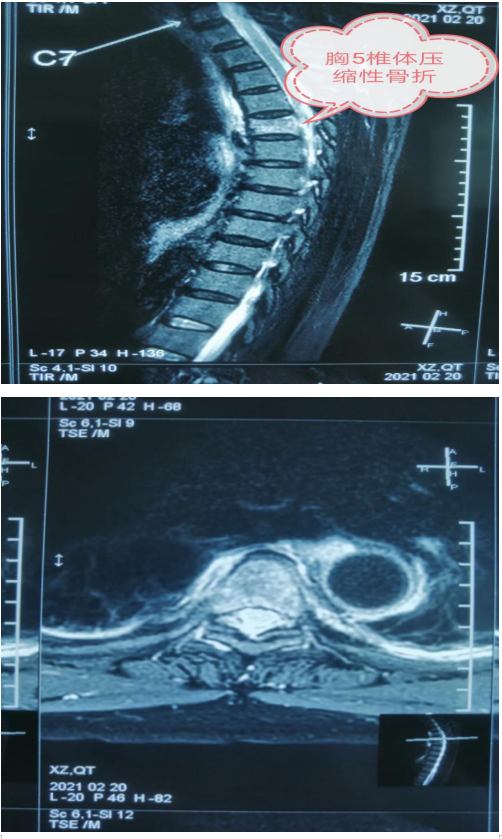

近日,一位76老年患者来我院就诊,患者过年骑电动车走亲戚不慎摔伤,高位胸椎5椎体压缩性骨折,乌海市人民医院骨科主治医师刘涛详细了解患者病情后予以手术治疗。术前,刘涛及脊柱外科组对患者手术部位进行了精准定位,既要保证手术高成效。有要避免伤及周边神经。术中,刘涛采用微创技术“胸椎骨折球囊扩张椎体成型术”,用球囊撑起患者碎裂脊椎,再用骨水泥进行填充。手术前后仅用时20分钟,手术中创伤小,出血少约5ml。手术效果立竿见影,术后患者胸背部受限感明显缓解,活动自如。翻身起坐疼痛感也大幅消失。